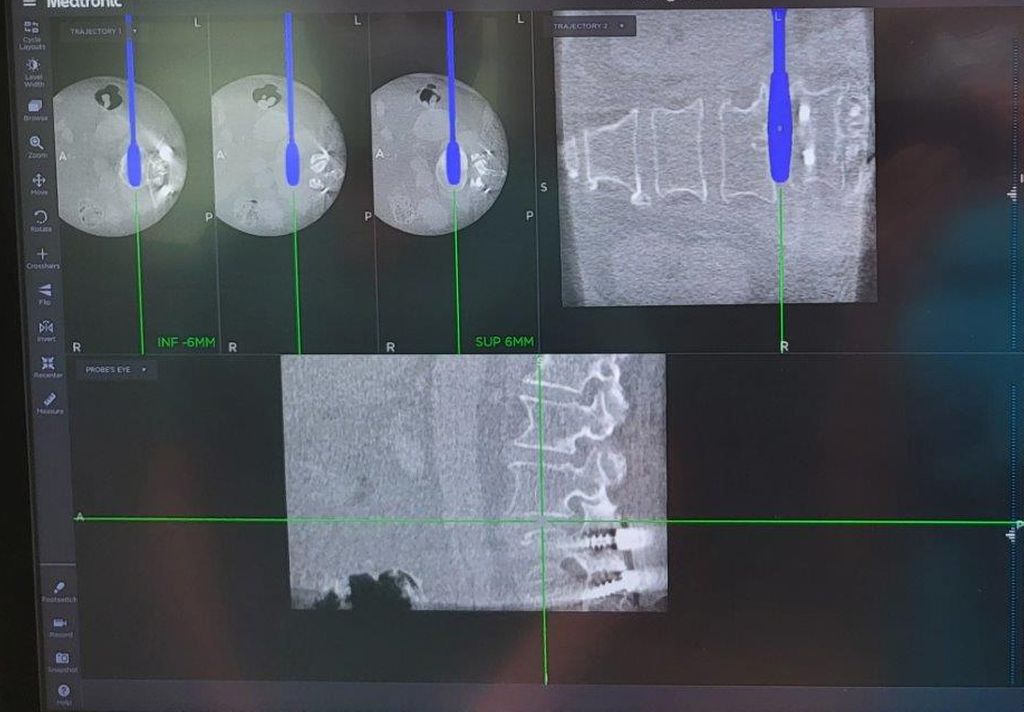

Beispiel für die Implantation zervikaler Pedikelschrauben. In diesem Fall kam es bei einem 61-jährigen Patienten 10 Jahre nach anteriorer zervikaler Diskektomie und Fusion (ACDF) C4/5 und ventraler Verplattung C4–6 zu einer Ankylosierung auch von C6/7. Nach Sturz kam es zu einer Fraktur bei C6/7 mit begleitender Bogenfraktur und auch Beteiligung der dorsalen Ligamenta (Abb. 1 und 2). Klinisch bestanden ausgeprägte Nackenschmerzen und kein neurologisches Defizit. Es wurde die Indikation der dorsalen Verschraubung von C4 auf Th1 gestellt. Intraoperativ wurde routinemäßig zusätzlich eine kleine Referenzschraube in einer Lamina – entfernt von der Dornfortsatz-Referenzklemme für die Navigation – gesetzt. Mit dieser konnte intraoperativ die Genauigkeit der Navigation exakt überprüft werden (Abb. 4 und 5). Mittels navigierter High-Speed-Fräse wurden die Schraubenkanäle vorgebohrt (Abb. 6), im Anschluss wurde der Bohrkanal ausgetastet und die Schrauben wurden implantiert. Abbildung 7 zeigt eine Röntgenkontrolle 3 Monate postoperativ.

Abb. 4: Screenshot der Navigationssoftware intraoperativ (Stealth Station S7). Es erfolgt die intraoperative Verifizierung der Navigationsgenauigkeit mittels kleiner Schraube in der Lamina, positioniert idealerweise entfernt von der Dornfortsatz-Referenzklemme. Die navigierte Fräse wird im Situs exakt auf die Schraubenmitte gerichtet, und die Navigation bestätigt die Genauigkeit | |